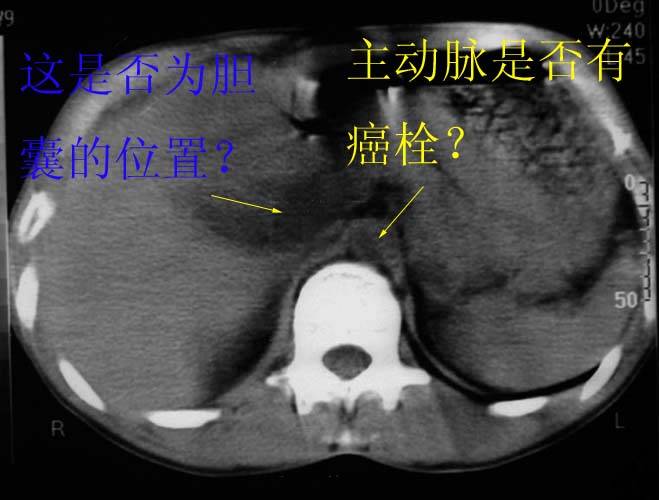

男,50y,右上腹包块痛10天,查:右上腹饱满,右肋下触及6*6cm大小包块,质硬,压痛。患者诉:10天前感冒胸闷,痛,后痛及右上腹部,既往有肝炎病史。

没有增强!只能考虑左叶内侧段巨块型肝癌(外生型)可能性大;胆囊呢?不除外胆囊癌累及肝脏。

我倒是先考虑胆囊癌(肿块型)肝脏受侵可能性大,做个c+

病变位于胆囊窝内,其内密度不均,肝总管及胆总管扩张,胃里面没有清水充盈,不解为什么楼主不做好了准备再做呢,支持:“左叶内侧段巨块型肝癌(外生型)可能性大;不除外胆囊癌累及肝脏”建议增强吧。

谢谢各位老师的指导学生还有几处不明白,请教。

考虑:肝左内叶巨块型癌,主动脉旁淋巴结转移.(有一层面似见胆囊受压.)